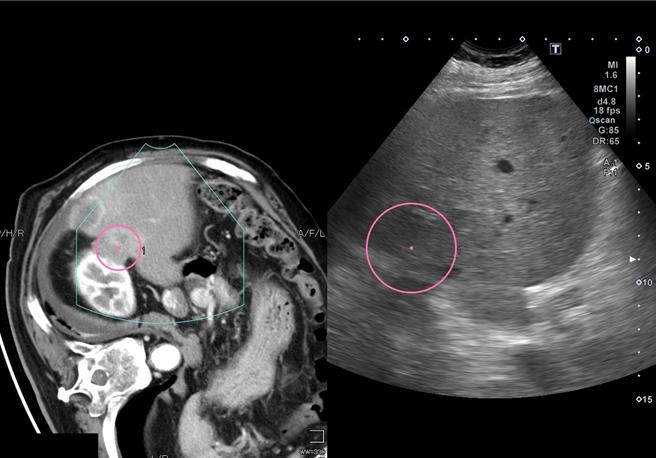

台中72岁张老板早年常应酬喝酒拚业绩,10年前罹患肝癌以手术切除8公分肿瘤,多年前復发以拴塞、放疗及标靶药物治疗控制,没想到近日三度復发,再採烧灼、免疫疗法治疗,仍维持良好生活品质。(亚大医院提供/潘虹恩台中传真)

张老板今年初追踪时,又发现1公分大的新生肝内小肿瘤,确认是復发的肝癌,使用射频烧灼术消除肿瘤,几个月后又发现3颗復发的肝癌肿瘤,接受经肝动脉血管栓塞化学疗法与免疫药物治疗。张老板日前回诊表示,身体健康稳定,还能跟家人一起外出旅游,并强调「信任医疗团队,只要活着就有希望」,鼓励抗癌的伙伴。